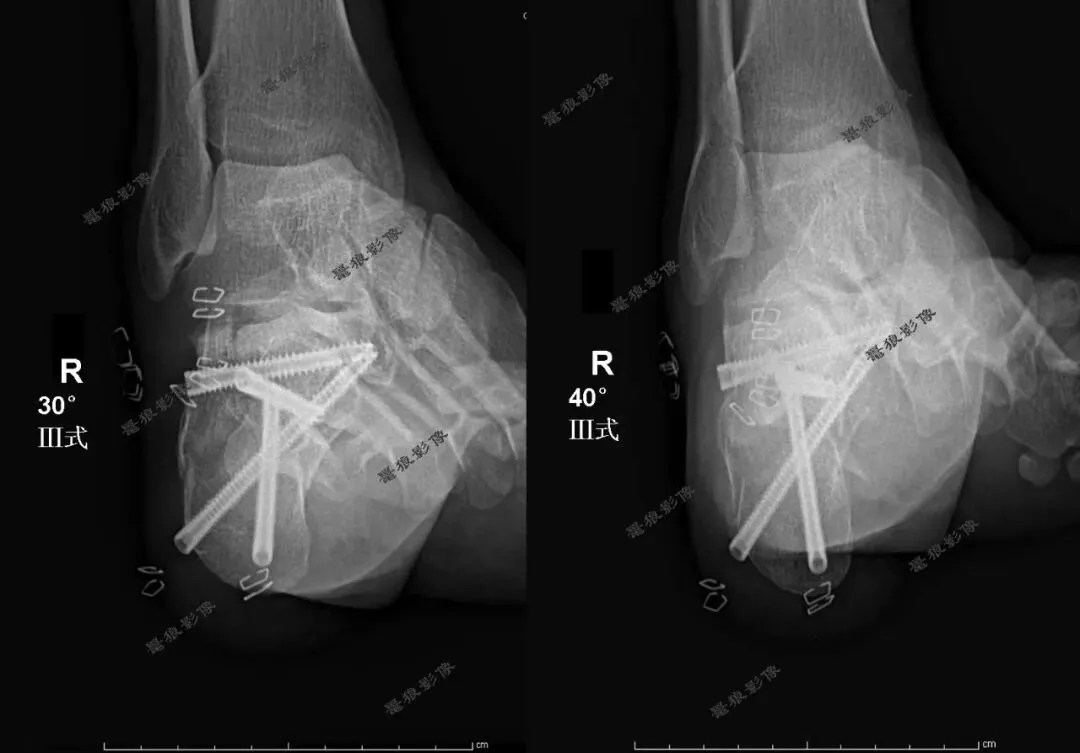

【学习笔记】跟骨Broden位(Ⅲ式)的临床应用